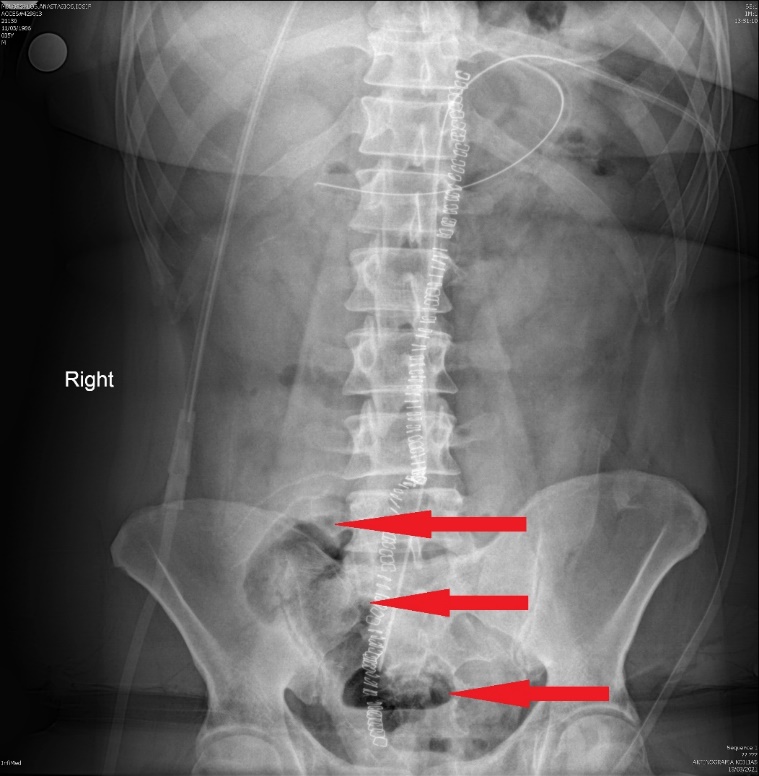

Καθολική γιγαντιαία διάταση ολόκληρου του κόλου (Ευγενική παραχώρηση Dr. V. Penopoulos)